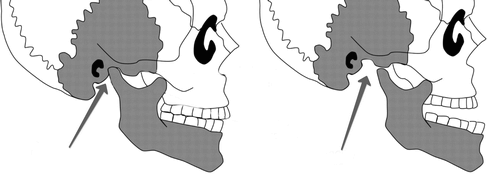

Вивих відбувається коли зміщується скронево-щелепної суглоб, тобто його головка вистрибує з ямки. Постійні такі травми можуть свідчити про дефекти будови суглоба: або занадто дрібні ямки, або дуже слабкі зв'язки. Якщо зсув тільки часткове, то повернення суглоба в природне положення відбувається без особливих зусиль, такий стан ще називають підвивихи.

► За розміщення головки скронево-щелепного суглоба щодо його ямки:

- задній - головка знаходиться позаду ямки,

- передній - найбільш поширений вид вивиху, головка знаходиться перед ямкою,

- бічний - головка збоку ямки.

- Нижня щелепа візуально подається назад щодо верхньої.

Як визначити бічний вивих? Для нього характерні ті ж ознаки, що і для заднього, але щелепа зміщена в бік по відношенню до вертикальної осі особи. У випадку з переднім вивихом, щелепу подається вперед по відношенню до верхньої.